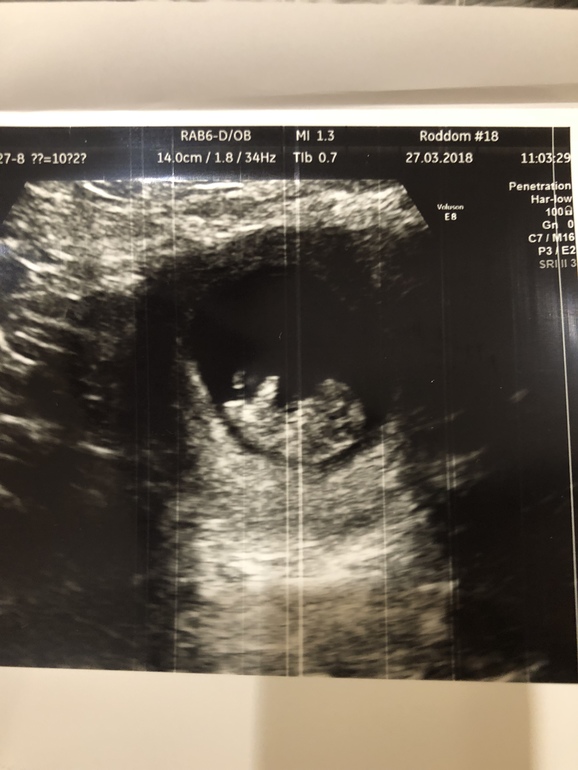

Первое узи

УЗИ, КТГ, доплерЕздили с девчонками в Питер, 27.3 сходила на УЗИ . Все у нас хорошо, человечек дрыгал ножками и ручками :) срок поставили меньше чем по мес. 9+5, плацента по передней стенке . Ну и собственно человек :)